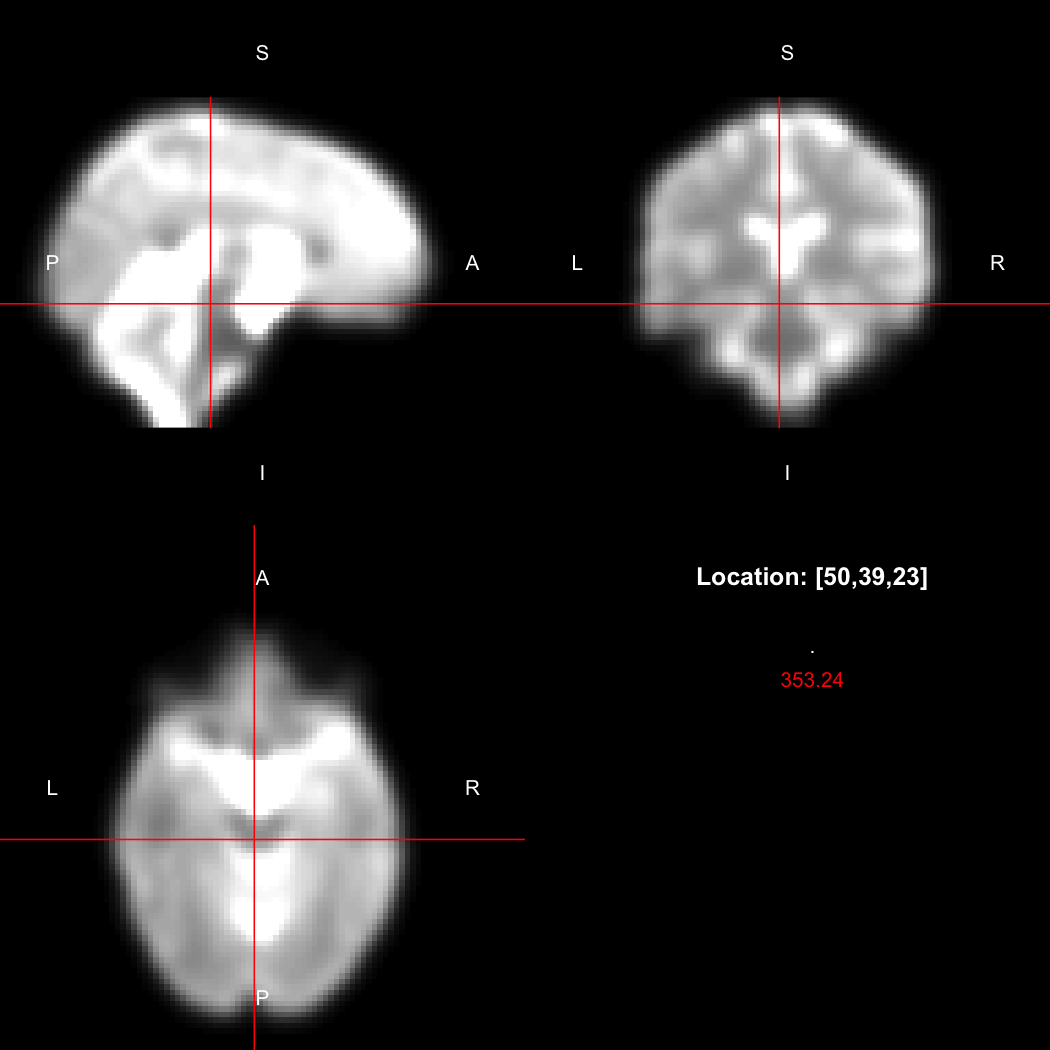

A simple example operation would be to smooth the image with a Gaussian smoothing kernel of standard deviation 4 mm. We can use standard R syntax to perform this operation, return a result, and then show it:

smoothed <- run(smooth_gauss(image, 4))

view(smoothed)

## Setting window to (0, 549.9)